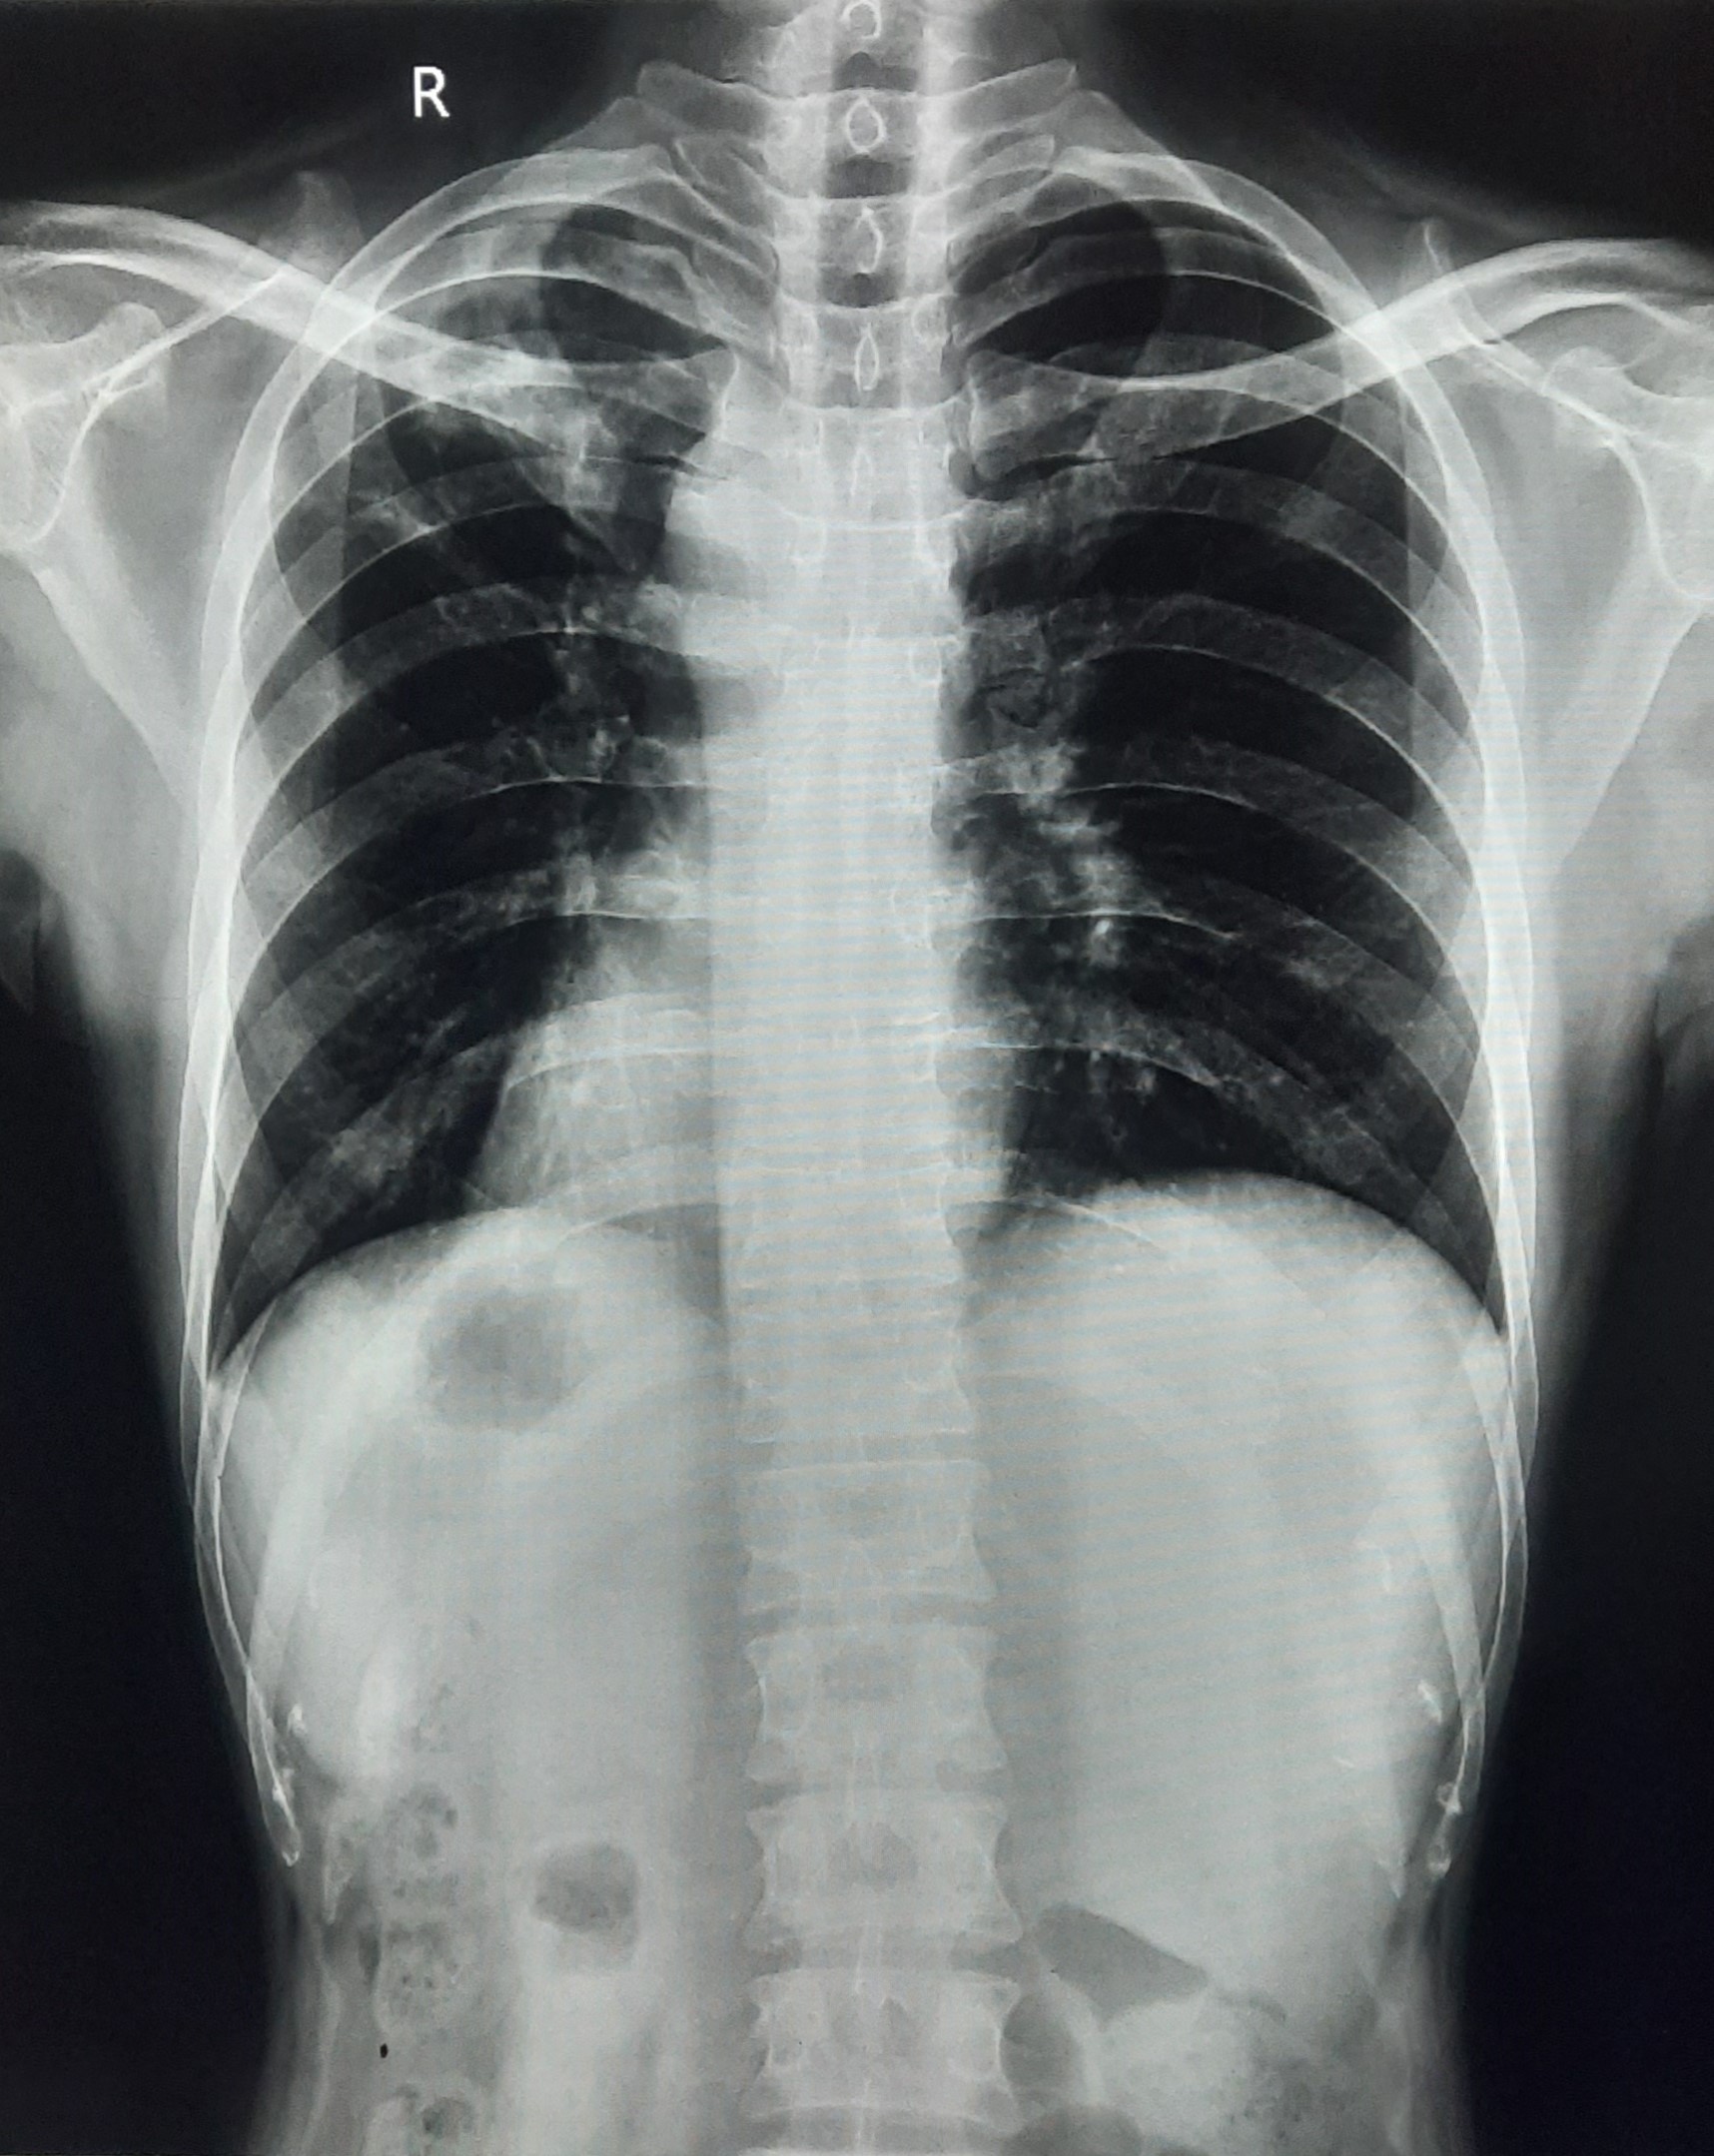

| 153 | IGGMC, Nagpur, Nagpur | P2 | 29-4319 | Irfan Ahmad | Consent taken on Paper | 59 Yrs. |

Provisional Diag : ?

Final Diag : Post TB Sequel With Reactivation |

Post TB Sequelae | Right Upper Zone/ Middle Zone Infiltration With Right Lower Zone Homogenous Opacity With Calcification | Abnormality visible on x-ray |